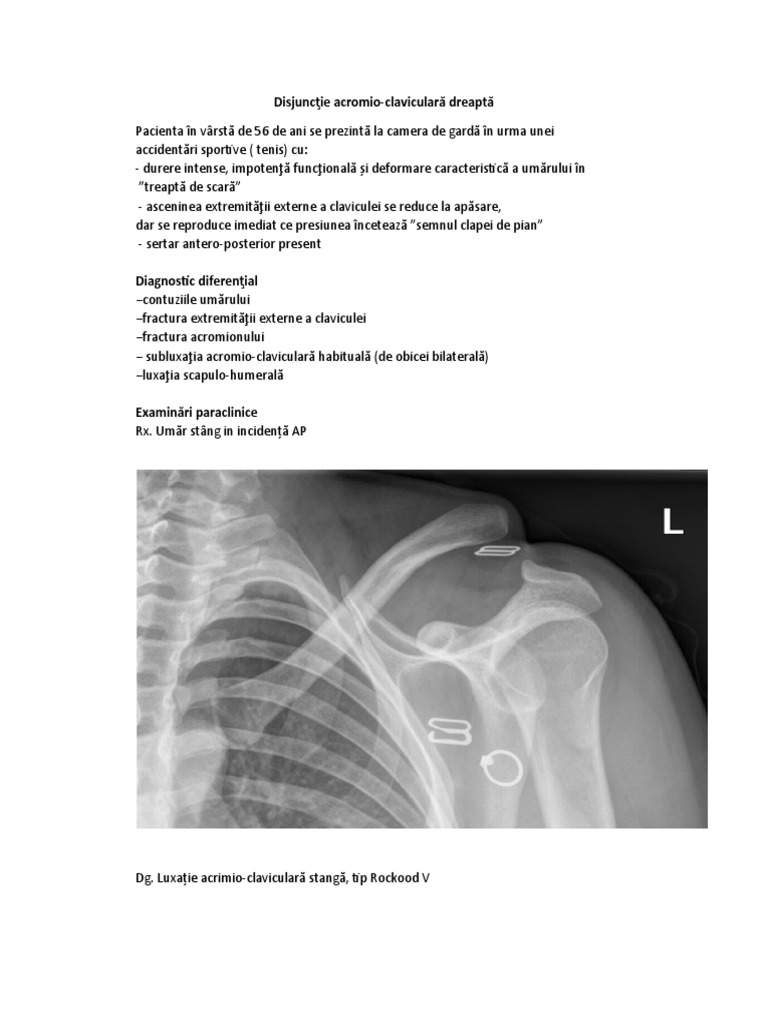

Notele muzicale pe clapele de pian alterate cu diez se cântă ca în imaginea de mai jos. Inlocuieste pianul acustic cu unuil digital cu caracteristici foarte bune. Apăsarea prelungită a clapei permite coardei să vibreze şi sunetului să se stingă de la sine. Acestă deformare se poate reduce relativ uşor dar reapare imediat după ce încetăm apăsarea pe claviculă semnul clapei de pian.

Aspect de treapta disjuncţia acromio claviculară. Din cauza ruperii legăturii dintre claviculă şi acromion umărul este mai căzut deplasare care devine mult mai evidentă în momentul în care pacientul încearcă să ţină în mână o greutate mare de exemplu o găleată cu apă. Uita de acordaje transport greu sau alte impedimente si alege unul din pianele digitale de la fly music. Definiții sinonime pentru clapă de pian din dicționarele.